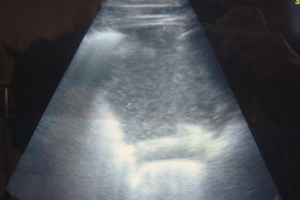

Pleuropneumonia

Pleuropneumonia is a relatively frequent condition diagnosed in horses we see. Using our on site laboratory and diagnostic ultrasound and radiology facilities, we are able to monitor responses to treatment very carefully.